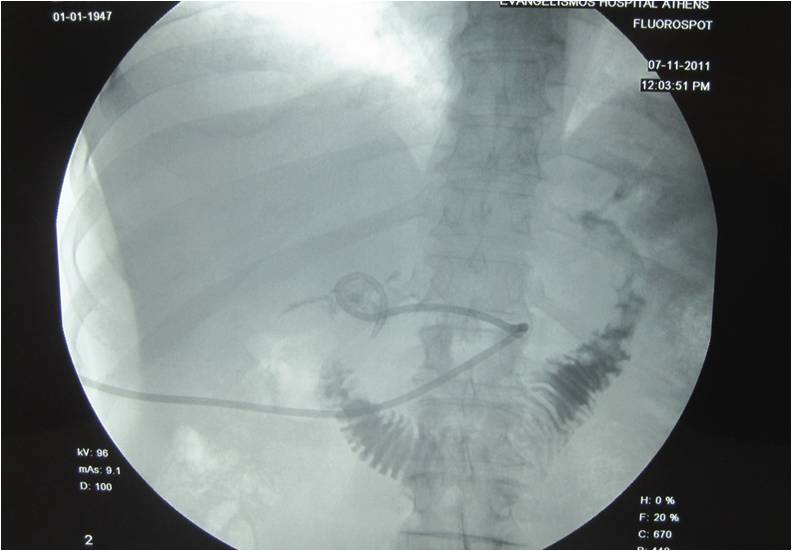

- Placement of a nephrostomy and sump caheter through the greater sciatic foramen into a deep pelvic abscess.